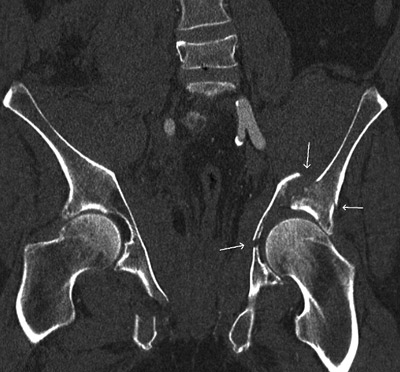

CT-undersøkelsene, som ble gjort omtrent to timer etter innkomst, avkreftet aortaaneurisme og alvorlig sykdom i hodet. Det var basale fortetninger i begge lunger. CT-undersøkelse av bekkenet viste multiple frakturer (fig 1, fig 2). På høyre side var det knusing av massa lateralis sacrii og en fraktur av fremre bekkenring med flere små fragmenter. På venstre side var femur trykt inn i bekkenet med en knusingsfraktur i acetabulum. Det var væske retroperitonealt og i muskulaturen i bekkenet. Mengden kunne ikke angis eksakt. På grunn av pasientens fallende blodtrykk og økende puls ble det startet kontinuerlig infusjon med noradrenalin i tillegg til pågående væskeinfusjon.

Ved ny klinisk undersøkelse viste det seg at smertene var lokalisert mer til bekkenregionen enn til ryggen. Pasienten var hemodynamisk ustabil, bekkenfrakturen var ustabil, og i tillegg var det acetabularfraktur. Bekkenfrakturen var den sannsynlige blødningskilde. Ortopedene bestemte seg derfor for å stabilisere frakturene med ekstern fiksasjon.